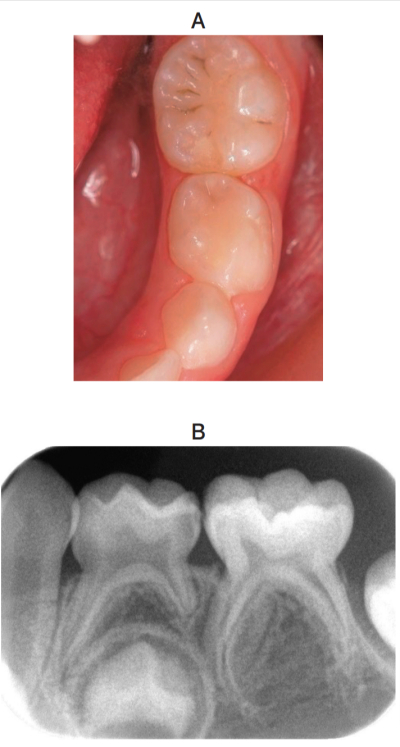

4歳6か月の男児。左側の下顎乳臼歯部の疼痛を主訴として来院した。1週前から痛みを感じるようになったという。⎾D は軽度の自発痛を認めるが、打診痛はない。初診時の口腔内写真とエックス線写真を別に示す。

最も適切な処置はどれか。1つ選べ。

a. 間接覆髄

b. 直接覆髄

c. 生活断髄

d. 抜髄

e. 抜歯